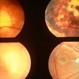

- Imaging device

- Fundus camera

- Right eye fundus photograph of 32-year-old gentleman shows a large peripapillary choroidal granuloma. Lymph node biopsy had confirmed systemic blastomycosis. The choroidal granuloma resolved with systemic and intravitral voriconazole.